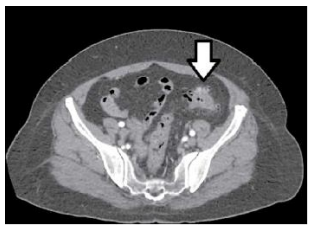

Paciente do sexo feminino, 45 anos, deu entrada no prontosocorro com queixa de dor abdominal baixa de início há 6 horas no hipogastro, com pouca resposta ao uso de analgésico em casa. Ao exame, apresentou-se estável hemodinamicamente, afebril, com dor à palpação no hipogastro e fossa ilíaca E, sem sinais de peritonite, sem massas palpáveis no abdômen. Realizada tomografia computadorizada, que produziu a imagem a seguir.

Com base nos dados apresentados, o diagnóstico para o caso em tela é: